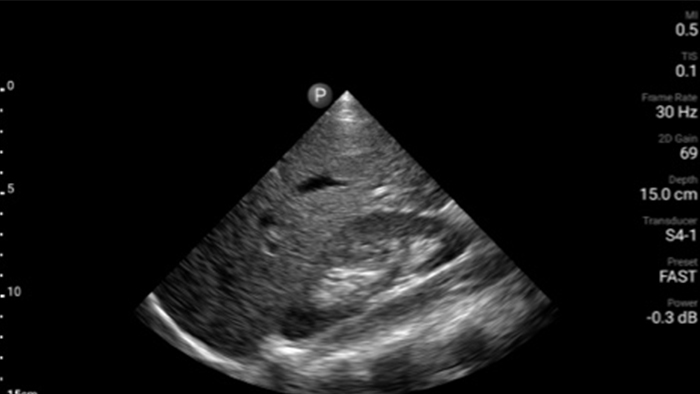

Lumify S4-1 broadband phased array transducer

• 4 to 1 MHz extended operating frequency range • 2D, color Doppler, M-mode, advanced XRES and multivariate harmonic imaging • High-resolution imaging for abdominal and cardiac applications: Cardiac, OB/GYN, Lung, Abdomen and FAST imaging preset optimizations